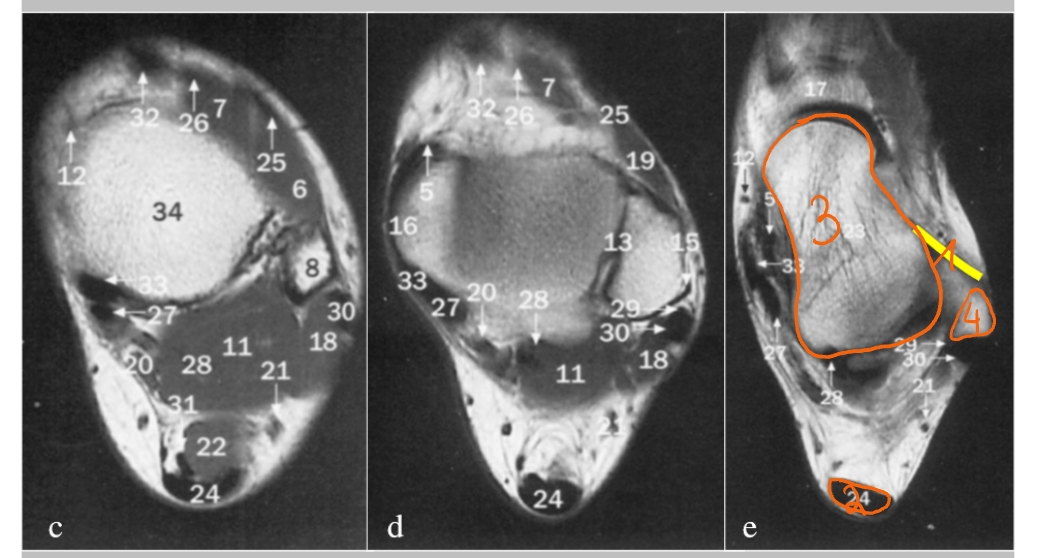

→ linker knie (MR): dwarse doorsnede

meniscus

anterieur

posterieur

pees van de m. quadriceps

patellapees

vetweefsel van Hoffa

voorste kruisband

achterste kruisband

meniscus (anterieur)

meniscus (posterieur)

tractus iliotibialis

mediaal collateraal ligament

lateraal collateraal ligament

→ linker knie (MR): coronale doorsnede